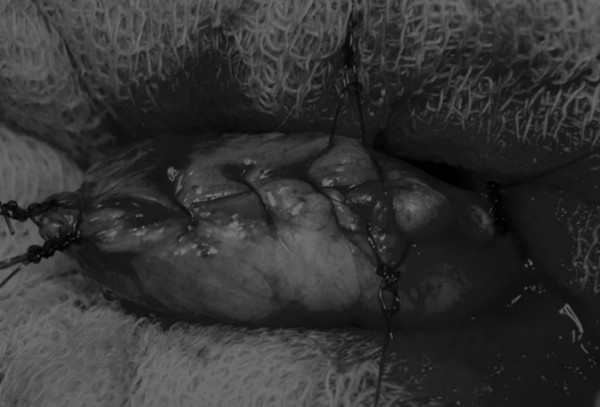

完成膀胱内冲洗后,应通过导尿管反向冲洗膀胱;砂样结石和血块会被冲到切口表面(图5)

图5 通过导尿管注入无菌生理盐水反向冲洗,可以去除微小的结石(箭头)和夹杂在膀胱黏膜皱褶中的砂样结石,以及可能在手术中形成的血块